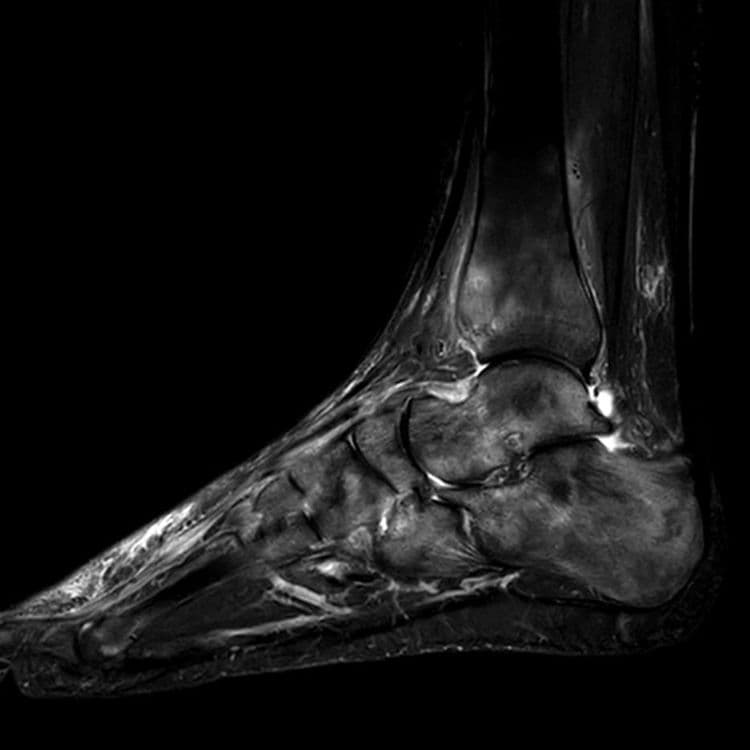

Algie aiguë plantaire d'un joueur de tennis de 50 ans

MRI